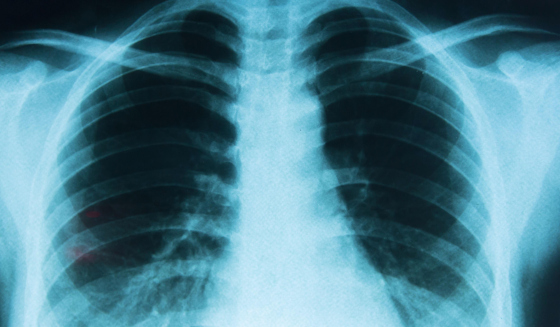

Une étude menée en Corée du Sud auprès de 8,4 millions de personnes (2021-2023) montre une augmentation significative de plusieurs cancers seulement un an après la vaccination : Thyroïde : +35% Gastrique : +34% Colorectal : +28% Poumon : +53% Poitrine : +20% Prostate : +69%

Étude rétrospective à grande échelle basée sur la population en Corée du Sud, portant sur 8.407.849 personnes de 2021 à 2023, avec des intervalles de confiance (IC) de 95%.

Les HR de la thyroïde (HR, 1,351 ; IC à 95%, 1,206–1,514), gastrique (HR, 1,335 ; IC à 95%, 1,130–1,576), colorectal (HR, 1,283 ; IC à 95%, 1,122–1,468), pulmonaire (HR, 1,533 ; IC à 95%, 1,254–1,874), mammaire (HR, 1,197 ; IC à 95%, 1,069–1,340) et prostatique (HR, 1,687 ; IC à 95%, 1,348–2,111)